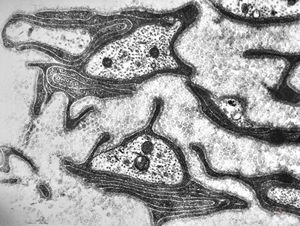

F,50y. | progressive multifocal leukoencephalopathy- viral particles in a glial cell